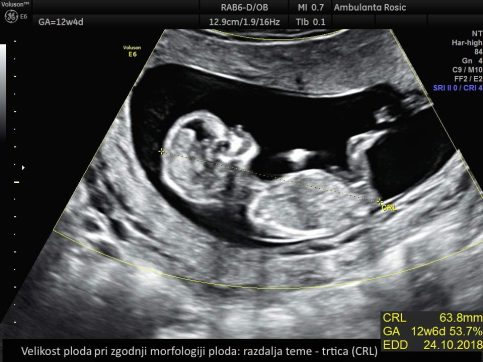

Pri preiskavi z ultrazvokom izmerimo debelino nuhalne svetline na plodovem zatilju. Poleg same meritve debeline nuhalne svetline preiskava zajema tudi meritev velikosti ploda, meritev hitrosti bitja njegovega srca, ugotavljanje prisotnosti nosne kosti in zgodnjo morfologijo ploda, kjer sistematično pregledamo plod in njegov razvoj v prvem trimesečju. Pri izračunu tveganja pa upoštevamo tudi starost nosečnice, saj imajo starejše nosečnice večje tveganje za rojstvo otroka z Downovim sindromom. Širša nuhalna svetlina pomeni večje tveganje za kromosomske nepravilnosti ter druge razvojne nepravilnosti, predvsem srčne napake. Pri velikosti nuhalne svetline nad 3,5 mm je zato svetovan podroben pregled plodovega srca v drugem trimesečju nosečnosti.

Preiskavo izvajamo med 11 0/7 in 13 6/7 tednom nosečnosti oziroma pri dolžini ploda med 45 in 84 mm. Izvajamo jo tudi pri dvojčkih. Opravljamo jo z ultrazvočnim tipalom preko trebuha, ob slabši preglednosti ali neugodnem položaju ploda pa skozi nožnico. Nosečnico prosimo, da pred pregledom popolnoma izprazni sečni mehur. Za natančno opravljeno preiskavo je pomembno, da je plod v pravi legi, zato pregled lahko pri različnih nosečnicah traja različno dolgo.